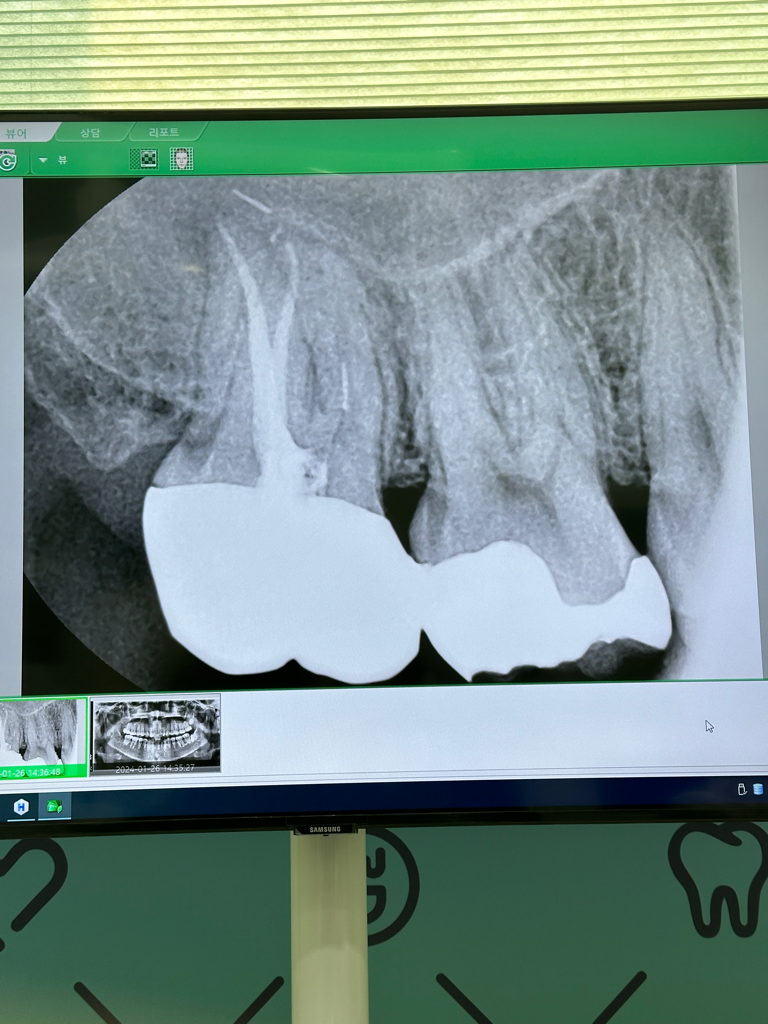

사진으로만 봤을 경우에는 신경관 중에 하나에 신경치료 도구가 부러져 있는 것으로 보입니다.

신경관내에 도구가 부러져 있게 되면 제거라는데 굉장히 힘이 될 수 있습니다. 치과에서 신경치료를 전문으로 하는 치과 보존과에서 진료를 받아 보는 것을 권유 드립니다.

제가 보기에는 근심쪽 (첫번째 큰 어금니와 가까운쪽) 치아 뿌리에 있는 신경이 제대로 신경치료가 마무리되지 않은 것 같습니다.

원심쪽 (먼쪽) 치아 뿌리 주변에는 염증이 잡혀 있습니다. 역시 다시 신경관을 채운 물질을 제거하고 깨끗이 소독하고 다시 재료를 채워넣는 재신경 치료가 필요할 것 같습니다.